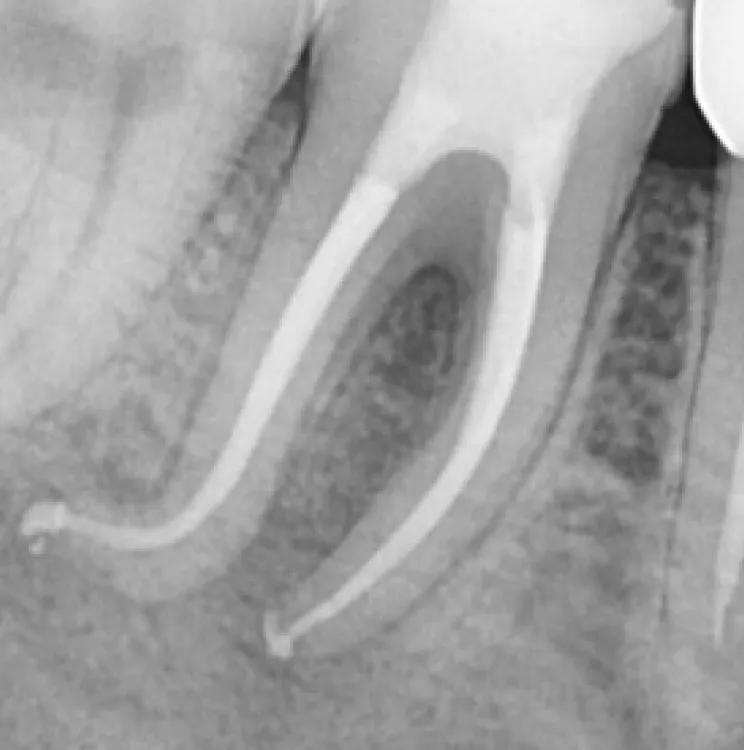

3

15 mois plus tard